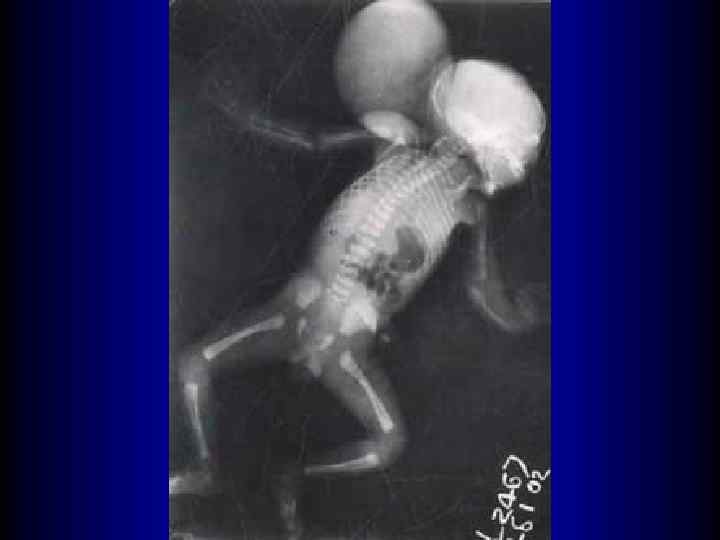

Синдром фон Восс-Черствого M. Urioste Azcorra, P. Aparicio Lozano. Sindrome de von Voss-Cherstvoy (DK-Focomelia): Primera descripciуn en Espaсa y revisiуn de la literature // An Esp Pediatr 1997; 46: 299 -302.